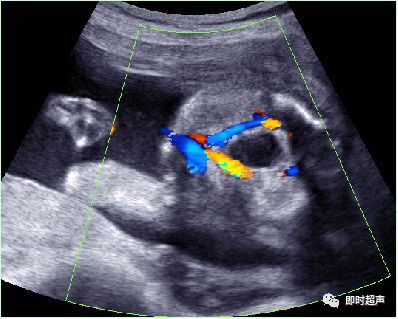

八、单脐动脉(SUA)

正常脐带内有两条脐动脉和一条脐静脉,供给胎儿营养。单脐动脉 , 指脐带内只有一条脐动脉和一条脐静脉,它是最常见的一种脐带异常。发生率约为0. 2% ~1.1%。

单脐动脉超声诊断

单脐动脉胎儿仅见一根脐动脉于膀胱一侧,经膀胱腹部横切面可判断左侧或右侧脐动脉缺如。羊水中脐带纵切面仅见两根血管并行或螺旋状排列, 横切时可见两个大小不一的圆环并行排列,彩色多普勒显示一红一蓝彩色血流信号。